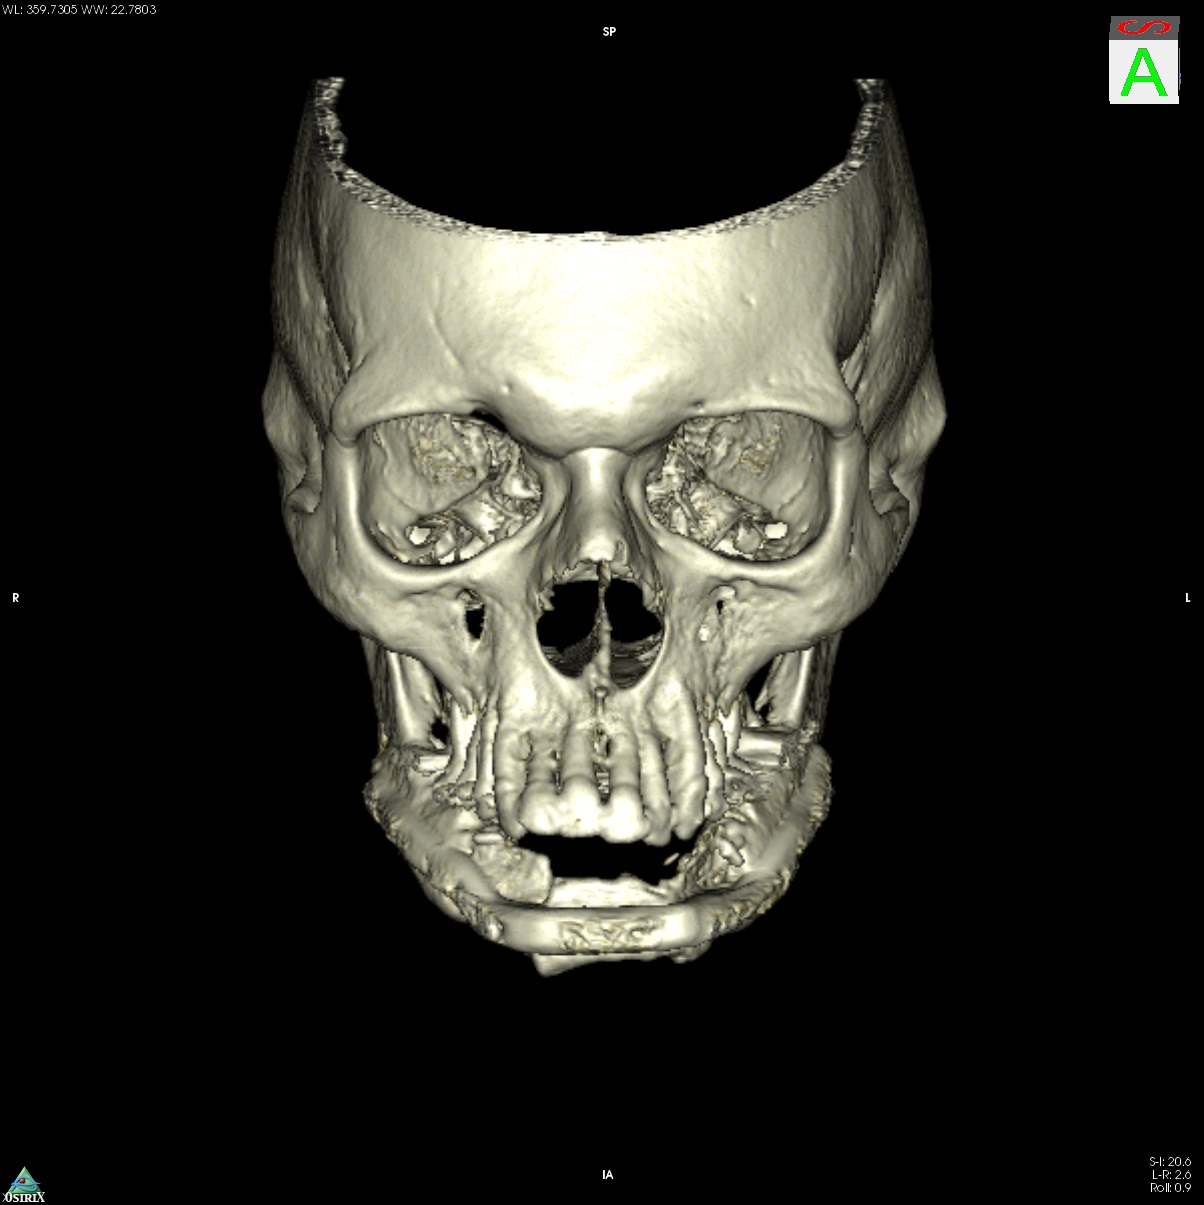

Computer-assisted planning (ProPlan CMF/TRUMATCH CMF Solutions) provides a virtual 3 dimensional model for a detailed osseous reconstruction of the maxilla or mandible with sub-segments of the lateral scapular border and/or tip (Fig. 1) based on high-resolution CT scans of the craniofacial skeleton and scapular region. To transfer such graphical representation accurately into real surgery requires an assorted toolkit of stereolithography (STL) models, selective laser sintered (SLS) templates for bone contouring and sub-segmentation osteotomies and patient specific implants (PSI).

A 58-year old male oncology patient required secondary mandibular reconstruction after composite resection of the floor of the mouth, mandibular symphysis, anterior body regions of the mandible and bilateral limited neck dissection. The existing reconstruction plate bridging the anterolateral mandibular defect was widely exposed through the intraoral mucosa. The chin and lower lip was sagging due to submandibular soft tissue shrinkage and lack of bone suspension. For secondary reconstruction, a two-in-one free flap from the subscapular vascular system containing the lateral scapular border and tip in combination with a latissimus dorsi flap was selected, since severe peripheral arterial occlusive disease prohibited the use of an osteofasciocutaneous fibula free flap. VSP was used to design the bony reconstruction with three sub-segments (total length 8.1 cm) from the right (nondominant arm) lateral scapular border and tip (Fig. 4).

Postoperative imaging confirmed minimal intersegmental gaps to the mandibular remnants with undisturbed healing but limited overall bone volume (Fig. 7a-c). Therefore removal of the PSPMP and a preimplantological augmentation with corticocancellous iliac bone grafts followed 16 months later.